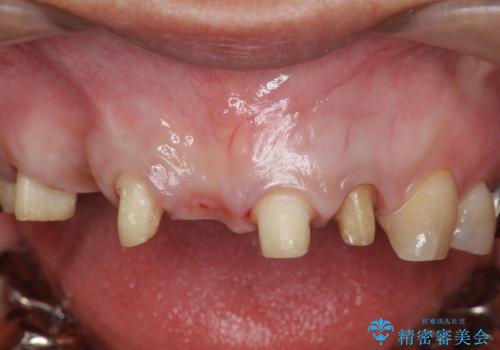

- 前歯を噛みしめにより失い、さらに犬歯もグラグラになり全く噛めなくなり改善を求めて来院されました。

過度な力がかかり周囲の骨に高度な吸収が見られた犬歯は抜歯し、機能・審美性の回復をより咬合力に対して抵抗力のあるブリッジ補綴にて対応します。

ブリッジによる欠損補綴を行ったのち、ナイトガードを夜間装着していただき歯を守ります。